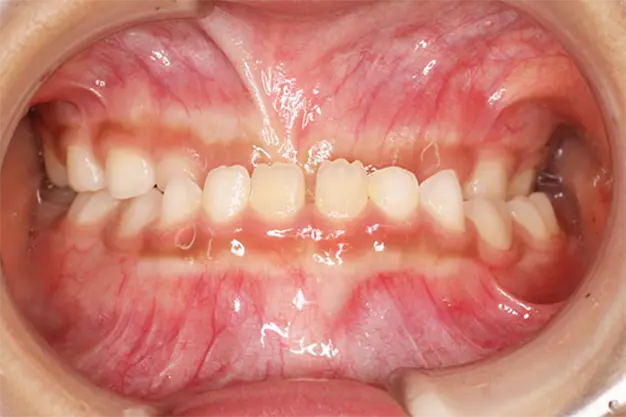

上下顎前突

上下両方の前歯が出ている

上の歯だけでなく下の歯も前に出ている状態を指します。噛み合わせが不安定になったり、特徴的な顔立ちになったりするだけでなく、発音や食事など日常生活にも支障をきたすことがあります。

- 診断名・主訴

上の内側に歯がある。下が特に歯並びが悪くいまだに乳歯が二本ある。

上下顎前突・軽度骨格性下顎前突・上顎前歯の唇側傾斜・叢生・下顎第二小臼歯の先天的欠如による第二乳臼歯の晩期残存・上顎右側側切歯の歯冠幅径不足(栓状歯)

- 年齢・性別

20代・女性

- 治療期間・回数

マルチブラケット動的治療期間 3年1ヵ月・24回

- 治療に用いた主な装置

◎セラミック製 唇側セルフライゲーション型ブラケット装置

- 抜歯部位

上顎両側4番・下顎両側E・上下顎8番(親知らず)

- 治療費

検査料 ¥50,000+消費税

装置料 ¥750,000+消費税

調整管理料 ¥3,000+消費税×回数

- リスク・副作用

歯肉退縮・歯根吸収・歯の移動時の痛み・咬合や装置の違和感・虫歯・歯肉炎・口内炎・後戻り